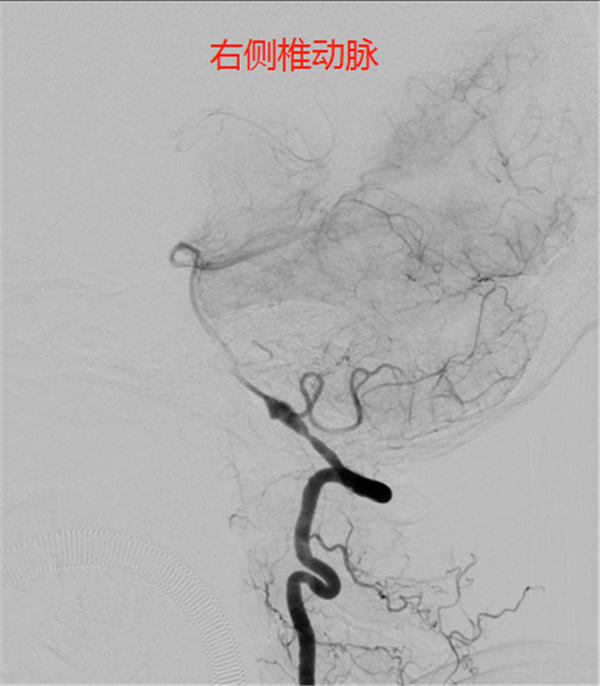

进一步的头颈CTA检查(如下图)证实了上述结论——谢女士的右侧椎动脉v4段长了一颗直径超过7mm的动脉瘤。虽然动脉瘤不属于肿瘤,但却存在破裂出血的致命危险。由于先天异常或后天损伤等因素,颅内动脉血管壁变薄甚至损坏,在源源不断的血流冲击下,就会形成一个突出的动脉瘤。它就像气球一样,在血流作用下可能越来越大,甚至破裂,导致颅内大出血甚至死亡,所以动脉瘤常常被比喻为“不定时炸弹”。

后对全脑血管进行造影,显示——

由于椎动脉属于后循环,管腔内径小,途径迂曲较多,导管到达动脉瘤部位难度较大,加之动脉瘤为梭型动脉瘤,PICA动脉自动脉瘤右侧发出,动脉瘤左侧有一小凸起,怀疑为动脉瘤破裂部位。

考虑到手术难度较大,4月3日,神经外科团队化身“拆弹部队”,用2小时的时间为谢女士实施了介入栓塞术,术中给予支架辅助下栓塞动脉瘤,术后动脉瘤闭塞,PICA动脉通畅,成功地将动脉瘤从脑血管中隔离出去。术后血管造影显示,动脉瘤已被弹簧圈填满,附近血管血流通畅。